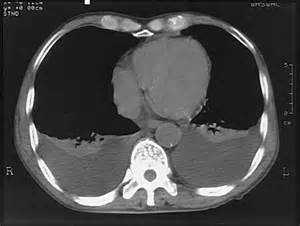

KT – plevral xəstəlikləri dəqiqləşdirən müayinədir.

Təcili xəstəliklərdə diaqnostika

Plevranın təcili müdaxilə tələb edən xəstəliklərinə pnevmotoraks, hemotoraks və massiv plevral maye aiddir. İlkin klinik-görüntüləmə müayinələrində təcili xəstəliklər olarsa əvvəlcə xəstəni stabilləşdirmək, sonra səbəbi araşdırmaq lazımdır. Stabilləşdirmək üçün (tənəffüsü və qan dövranını bərpa etmək) oksigenoterapiya və plevral drenaj gərəkir. Səbəbin müəyyənləşdirilməsi üçün isə klinik məlumatlar, KT və plevral mayenin müayinəsi nəzərə alınır (Şəkil 2).